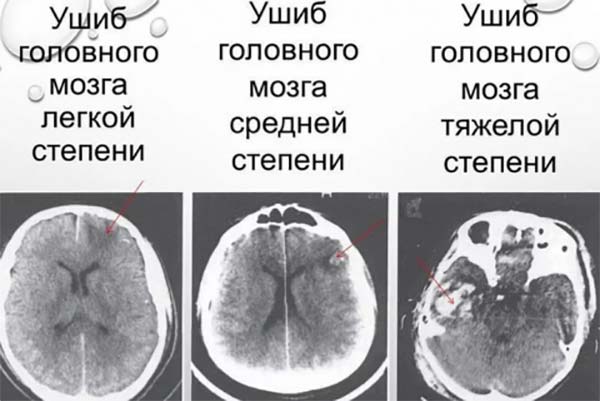

Доктора умовно розрізняють три ступені тяжкості закритої травми голови. Температура в даному випадку буде непрямим показником.

Іноді ступінь тяжкості травми не може бути визначена в першу добу. Щоб поставити остаточний діагноз, медикам потрібно подивитися на характер перебігу хвороби у розвитку.